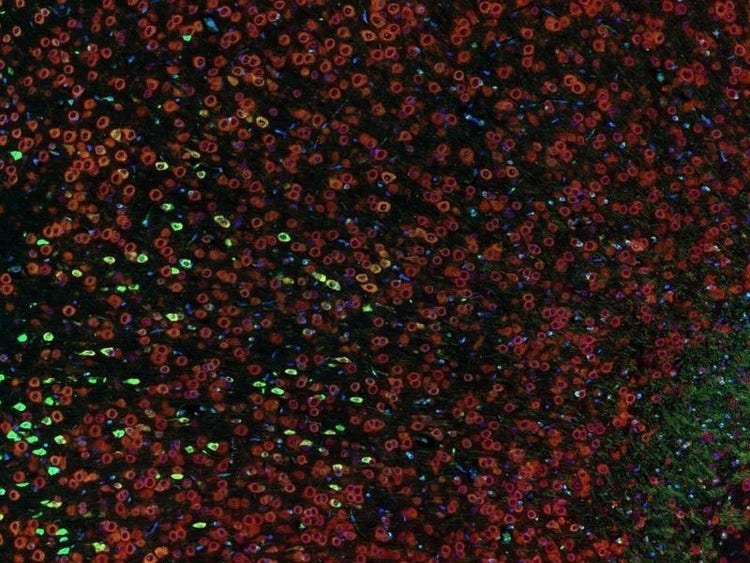

Fluorescence imaging of a mouse brain

Jedes dieser Bilder sieht aus der Nähe anders aus, aber sie fügen sich zu einem Bild eines Mäusegehirns zusammen, das mit Fluoreszenzbildgebung aufgenommen wurde.

Der britische Wissenschaftler Sir George G. Stokes beobachtete zum ersten Mal, dass das Mineral Flussspat fluoresziert, wenn es mit ultraviolettem Licht beleuchtet wird, und prägte den Begriff „Fluoreszenz“. Stokes fand heraus, dass das fluoreszierende Licht eine größere Wellenlänge hat als das Anregungslicht, ein Phänomen, das heute als Stokes-Verschiebung bekannt ist. Die Fluoreszenzmikroskopie ist eine hervorragende Methode zur Untersuchung von Materialien, die entweder in ihrer natürlichen Form (Primär- oder Autofluoreszenz) oder nach Behandlung mit fluoreszierenden Chemikalien (Sekundärfluoreszenz) fluoreszieren können.